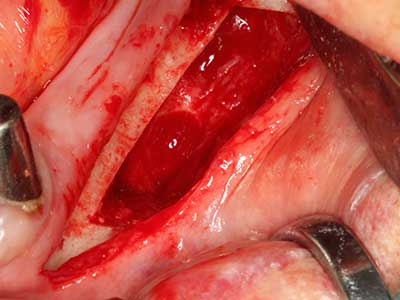

Indikation: Wurzelspitzenresektion

Sollen chirurgische Eingriffe mit unmittelbarer Knochenbeziehung an empfindlichen Strukturen wie Blutgefäßen oder Nerven erfolgen, so bergen rotierende Instrumente ein erhebliches Potential an iatrogener Schädigung. Gerade bei Nervdarstellungen nach iatrogener Schädigung, oder aber im Zuge einer Nervlateralisation für resektive und rekonstruktive Eingriffe oder Implantatinsertionen können piezoelektronische Geräte hilfreich sein Knochendeckel zu präparieren und nervnahe Hartgewebsanteile zu entfernen (Abb. 17-20). Ein leichter Kontakt des Nervstrangs zur Piezospitze bleibt dabei in der Regel folgenlos – allerdings kann eine unvorsichtige Vorgehensweise mit sägeartigen Bewegungen bzw. Ansätzen bei noch vorhandener knöcherner Unterlage durchaus temporäre oder aber auch permanente Nervschädigungen verursachen. Das Risiko einer solchen Schädigung wird jedoch als wesentliche geringer eingeschätzt als unter Anwendung von Säge- oder Fräsinstrumenten (Pereira, Gealh et al. 2014).